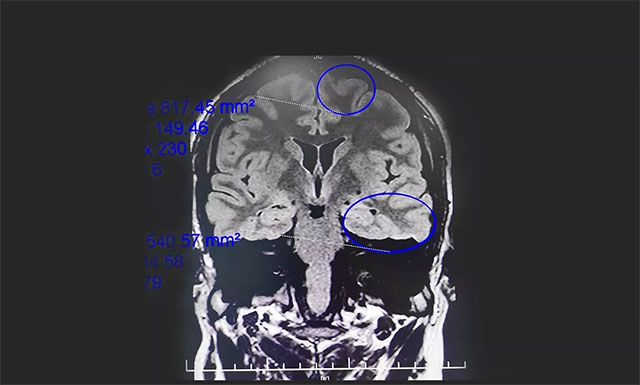

▲ 通過(guò)系列檢查最終明確患者致癲灶

腦電監(jiān)測(cè)崔麗華主任根據(jù)腦電圖監(jiān)測(cè)分析指出,患者雙側(cè)有癲癇波,左側(cè)較為嚴(yán)重。磁共振檢查,患者顳葉、額葉、海馬結(jié)構(gòu)異常。既往史顯示,患者1歲時(shí)有多次高熱病史,并伴抽搐。

患者經(jīng)系統(tǒng)內(nèi)科藥物治療不佳,確診為藥物難治性癲癇,經(jīng)過(guò)系列檢查最終明確患者致癲灶位于左側(cè)顳葉、左側(cè)額葉、左側(cè)海馬。手術(shù)指征明確,未見(jiàn)明顯手術(shù)禁忌癥。